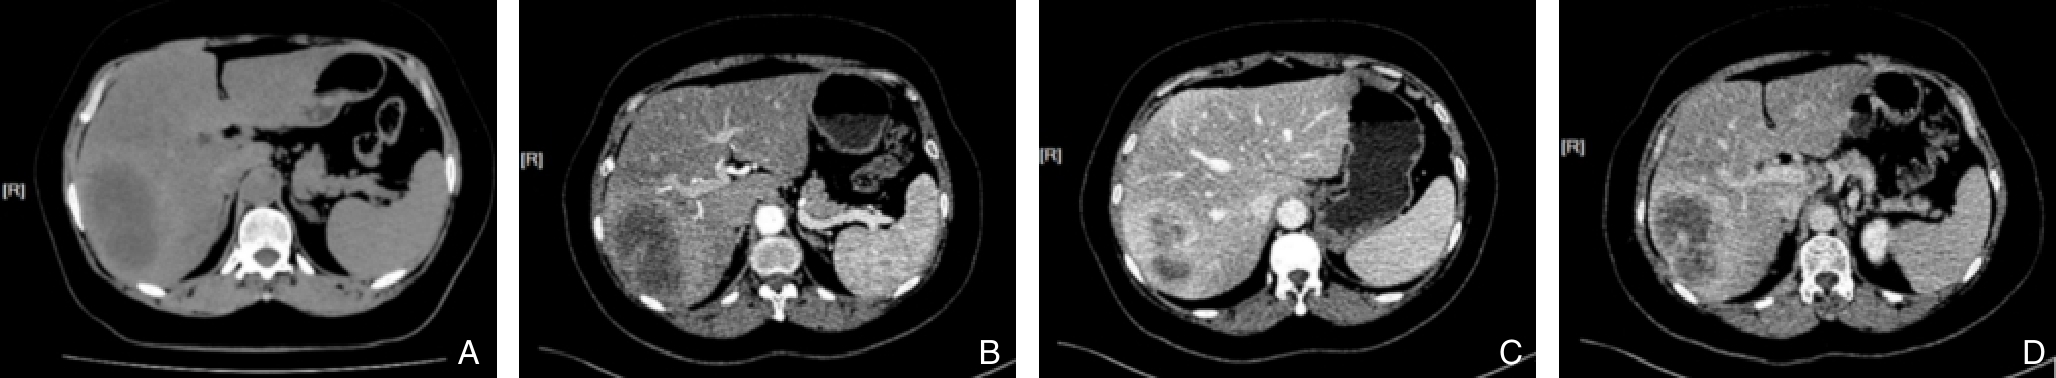

摘要:背景与目的 腹主动脉瘤(AAA)是血管外科常见的动脉扩张性疾病,其最严重的并发症为瘤体破裂,常引发致命性大出血,严重威胁患者生命安全。腹主动脉瘤腔内修复术(EVAR)因其微创、安全、恢复快的优势,已成为AAA的首选治疗方式。然而,术后特有的内漏并发症仍是当前临床面临的主要难题。内漏可致瘤腔持续高压,增加瘤体扩张及破裂风险,是EVAR术后二次干预率较高的主要原因之一,尤其Ⅱ型内漏的处理策略尚存争议。本研究旨在评估在标准EVAR术中联合经髂动脉入路选择性瘤囊栓塞技术治疗即刻内漏的临床应用价值。 方法 回顾性收集2023年3月—2024年9月在中国医科大学附属第一医院接受标准EVAR治疗并有内漏风险的AAA患者临床资料。根据是否实施术中经髂动脉入路选择性瘤囊栓塞分为干预组(42例)与未干预组(32例),比较两组患者的一般资料、术前AAA解剖学特征、手术细节及术后随访结果。 结果 两组患者在年龄、性别、解剖特征、破裂率及超说明书使用比例等方面差异无统计学意义(均 P>0.05)。两组术中技术成功率均为100%。干预组1例术后出现一过性乙状结肠缺血,经保守治疗好转。平均随访时间为(6.49±4.68)个月,干预组瘤囊缩小、稳定及增大比例分别为40.5%、57.1%和2.4%,未干预组分别为59.4%、40.6%和0.0%,两组间差异无统计学意义(均 P>0.05)。随访期间内漏发生率在两组间亦无明显差异( P>0.05)。 结论 对于标准EVAR术中出现的内漏,经髂动脉入路选择性瘤囊栓塞技术操作简便、安全,短期疗效与术中无内漏者相当,值得临床推广。其远期疗效仍需进一步随访验证。